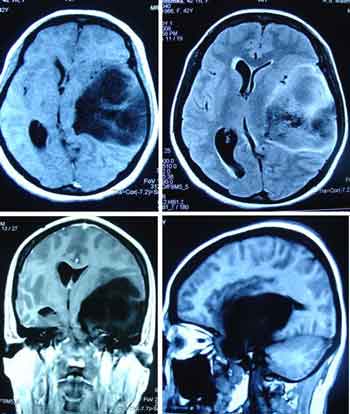

Brain Cancer – Yet She Lives !

CT, 42 years old, came to see us in September 2008. There was a tumour in her head. The neurosurgeon in a private hospital in Penang told the family that she must undergo surgery immediately. Without the surgery CT would become blind and paralysed. If she underwent surgery, there was no guarantee that she would be cured.

The family decided against further medical treatment and came to seek our help on 12 September 2008. CT was prescribed Capsule A, Brain 1 and Brain 2 teas, C-tea + Brain Leaf tea.